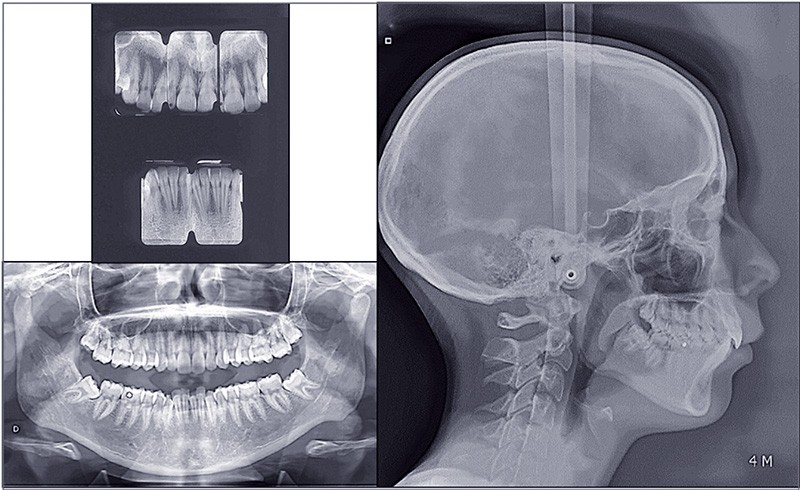

À l’examen des radiographies, la formule dentaire est complète avec 38 et 48 en mésioversion sous la face distale de 37 et 47. Il n’y a pas d’anomalie de la voûte et de la base du crâne.

L’analyse céphalométrique révèle une typologie normodivergente tendance hyperdivergente (FMA = 29°), et une classe II squelettique (ANB = 8°, AoBo : 6,5 mm) par rétrognathie mandibulaire (SNB : 75°).

L’incisive mandibulaire est vestibuloversée (IMPA : 98°) (fig. 2).